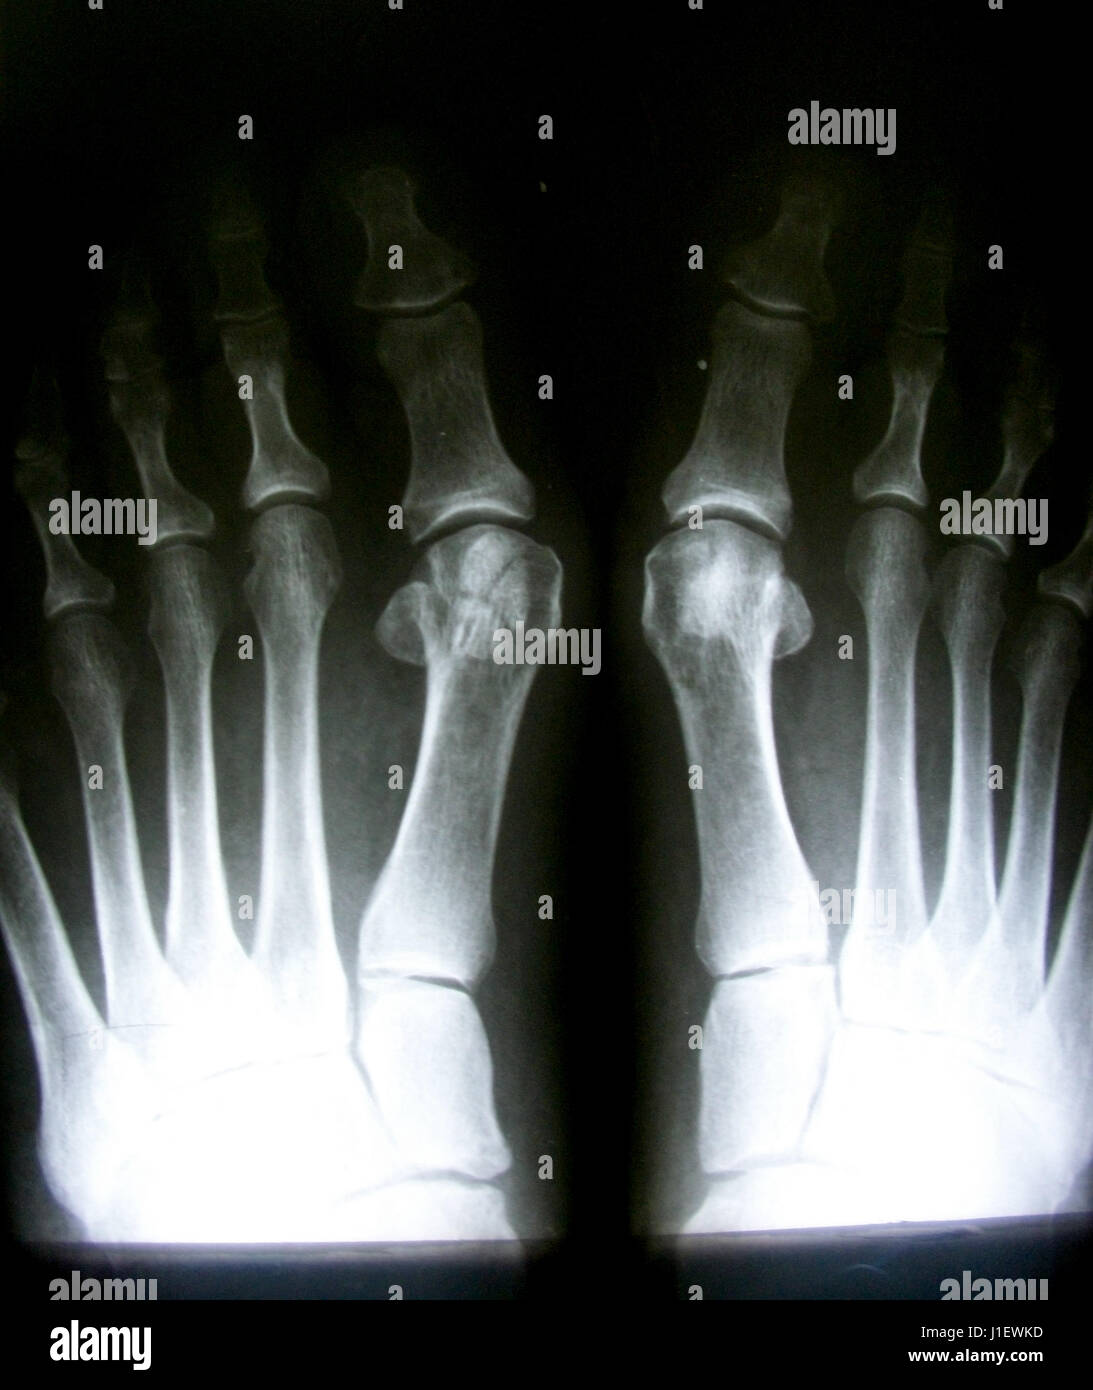

Röntgenbild Des Normalen Fuß Beidseitig Stockfotografie – Alamy

www.alamy.de